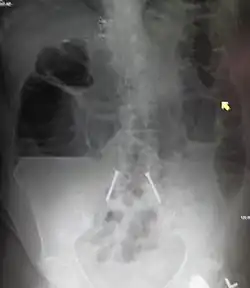

Upright abdominal X-ray of a person with a large bowel obstruction showing multiple air fluid levels and dilated loops of bowel